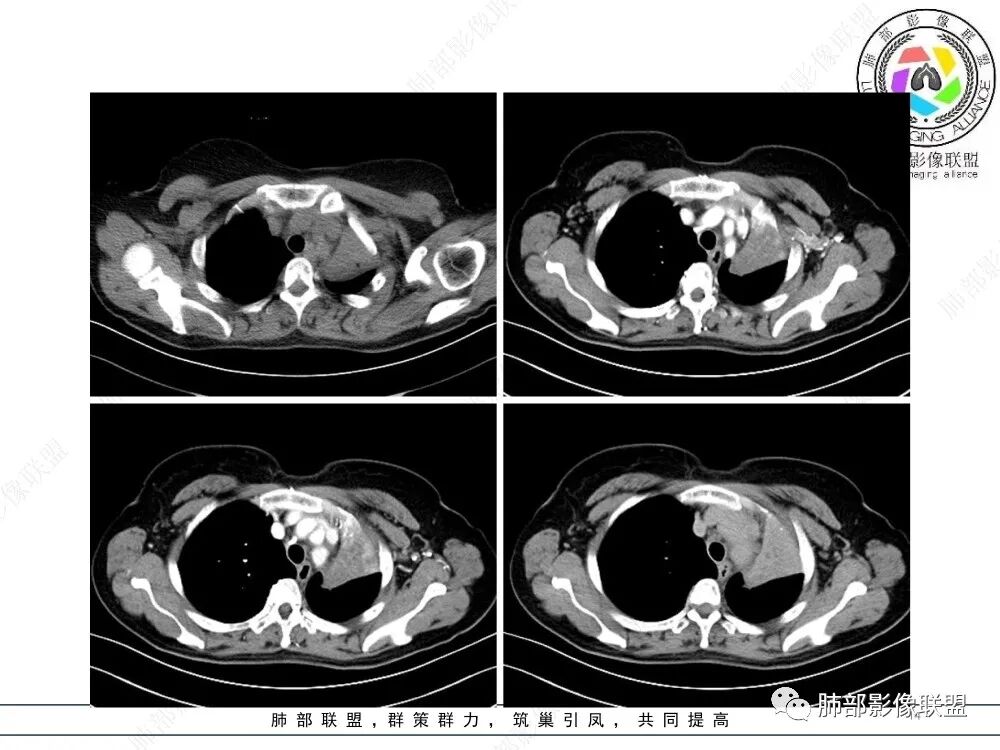

2、影像表现:正常肺背景,左肺上叶支气管腔内占位,上叶支气管截断,远端肺组织不张,强化差异衬托出肺门区结节影或块状影。增强扫描腔内占位轻中度不均匀强化,可见坏死,远端粘液栓,局部肺动脉受压、侵犯,纵膈淋巴结无明显肿大,无胸腔积液。

3、综合分析:老年女性,支气管腔内占位明确,病灶向周围侵犯,诊断恶性肿瘤并肺不张问题不大。需要考虑到的疾病谱有鳞癌、腺样囊性癌、粘液表皮样癌、类癌、小细胞肺癌等。